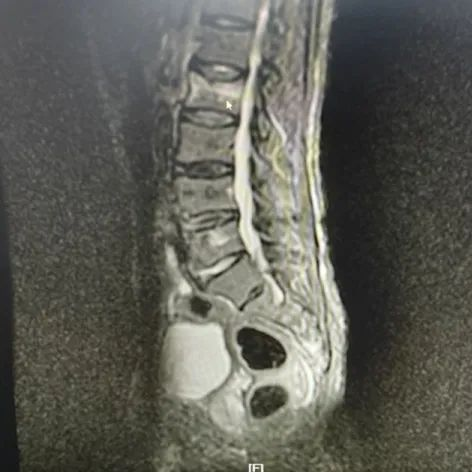

不久前,89岁高龄的翟老太不慎跌伤,导致腰椎骨折,因为剧烈疼痛,老人不能坐也不能站,只能侧卧在床,连翻身、吃饭都很困难。看到蜷缩在床上不断呻吟的老人,家人焦急万分,听说姜堰中医院骨伤科陈成团队擅长治疗腰部损伤,急忙将老人送到我院骨科就诊,经医生诊断翟老太系腰椎骨折。

翟老太被收治到我院八病区后,脊柱骨科夏国栋副主任医师为老奶奶制定了详细的诊疗方案,决定采用经皮椎体成形术为老人手术。一听说要手术,躺在病床上的翟老太就急了,连连摆手,嘟囔着说“不,不...”夏国栋医师笑着安慰老人及家属,并详细解释了经皮椎体成形术的手术方法,消除了翟老太和家人对手术治疗的疑虑。夏国栋诊疗组的专家在手术室给翟老太腰上打了“一针”,手术时间仅20多分钟,回到病房的翟老太腰部疼痛消失,当天就基本恢复到受伤前的状态。立竿见影的手术效果令翟老太的家人们啧啧称奇!出院后的翟老太嘱咐家人给医生送来锦旗。

翟老接受的经皮椎体成形术(percutaneous vertebro plasty,PVP),属于微创手术,是通过精确定位向病变椎体内注入骨水泥(聚丙烯酸甲酯,polymethylacrylate,PMMA)达到治疗作用的技术。此种手术通常采用局部麻醉,麻醉风险低,手术伤口约2毫米,出血约5-10ml,手术时间20-30分钟左右。术后就能感觉腰痛减轻,第二天就能起床活动,逐渐恢复起居、行走等日常活动。

据了解,对于老年腰椎骨折,传统治疗多采用保守治疗,要求绝对卧床3月加药物治疗。但是老年人往往伴有高血压,糖尿病,心脏病等基础病,长期卧床容易并发肺部感染、血栓、褥疮、尿路感染、感染性休克等疾病,继而危及生命。近年来,微创化手术逐渐成为此类疾病的主流方案,经皮椎体成形术技术可以稳定脊柱、快速止痛、见效快、效果好,可大大减少患者的卧床时间,明显提高患者的生活质量,帮助患者早日恢复正常生活。夏国栋副主任医师所在的姜堰中医院脊柱骨科具有脊柱微创手术成熟的技术,大量脊柱骨折病人在微创手术后像翟老太一样撑起了脊梁,恢复了健康。